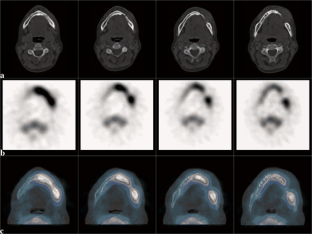

Abb. 1 a–c: